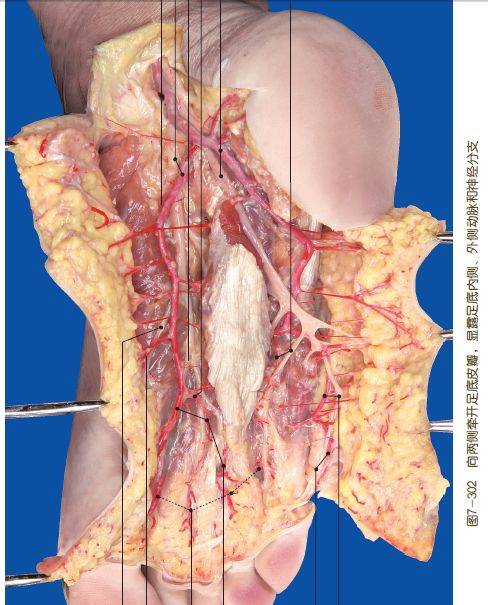

这是书中的部分解剖图片